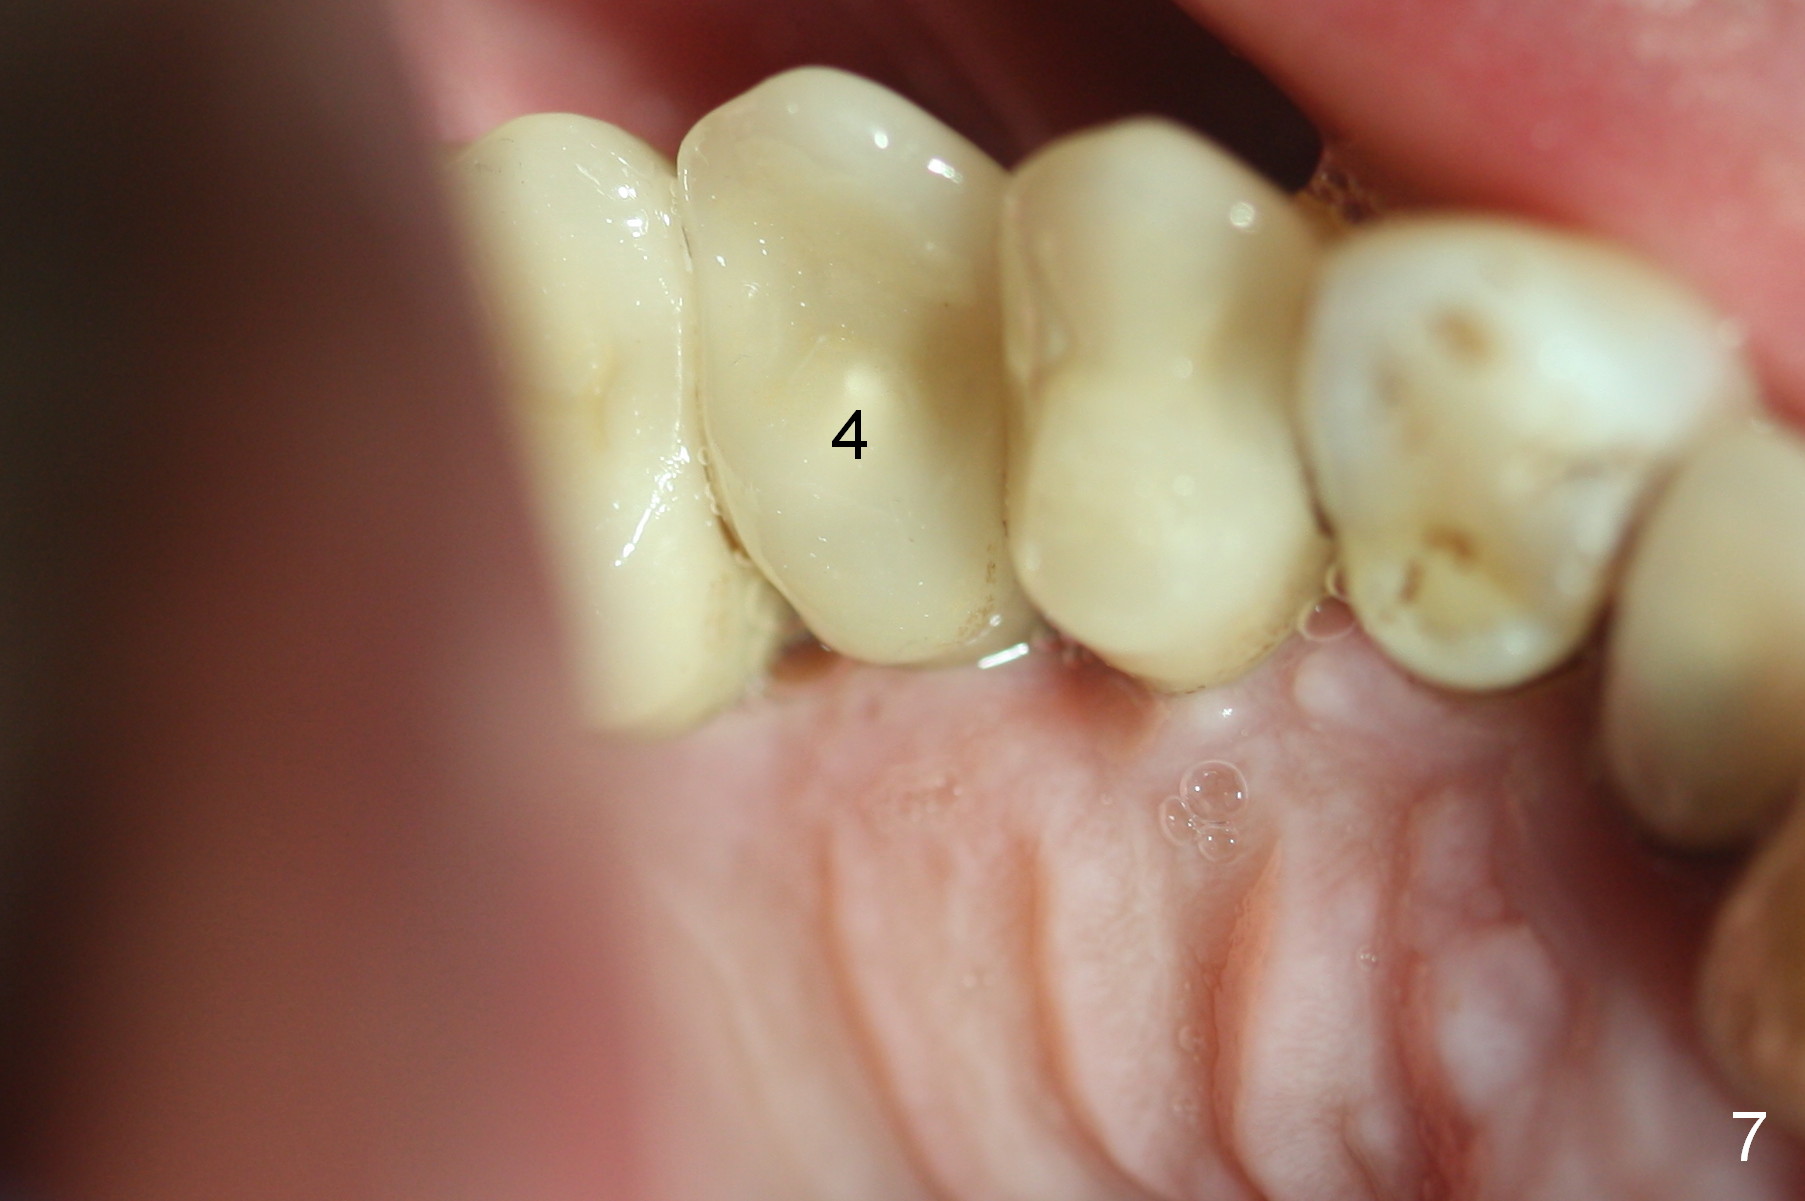

The patient returns for follow up 3 months postop. There is no gingival bleeding around the site of #4 palatally (Fig.7) or buccally (Fig.8). There is no further bone resorption (Fig.9).